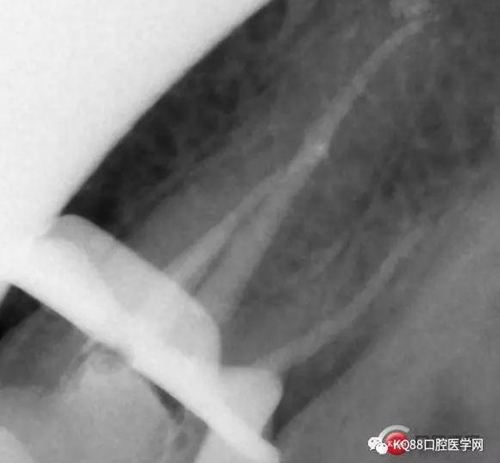

此次明顯可以看見(jiàn)根尖分開(kāi)了兩個(gè)根尖孔,根管治療永遠(yuǎn)就只是那一點(diǎn),如果都只是隨便做一下,我相信,沒(méi)有復(fù)雜的牙齒,根管治療都會(huì)很簡(jiǎn)單,態(tài)度決定一切,我不敢說(shuō)我做的會(huì)很好,但是我會(huì)靜下心來(lái),慢慢操作,這樣才能做得對(duì)的起自己和患者。于是根充完成,再次拍攝。

Y形態(tài)變形成了,根間支也明顯出現(xiàn),充填嚴(yán)密,雖然根管治療的成功率不是一百,但是我們盡可能把那一點(diǎn)做到位,往往結(jié)果可能會(huì)很驚人,如果我在第一次就充填了,可能也不會(huì)有什么錯(cuò)誤,但是態(tài)度就已經(jīng)輸了,我們基層做根管不會(huì)像武大等那么規(guī)范,但是也希望可以向其靠攏,一個(gè)好的根管,上面才能有美的修復(fù)。